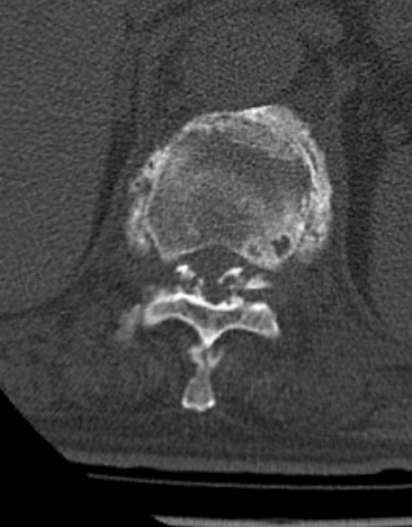

此次正逢中南大学湘雅医院脊柱外科专家邓盎教授来湘潭市中医医院坐诊,患者慕名前来。邓盎通过详细询问病史、体格检查,并结合脊柱CT、MRI等影像学检查结果,明确诊断患者为胸椎Chance骨折保守治疗不愈合、胸椎黄韧带骨化,胸椎椎管狭窄。

医生介绍,胸椎Chance骨折是一种特殊类型的脊柱屈曲-牵张性损伤,常累及脊柱后柱结构,而黄韧带骨化会进一步压迫脊髓,导致神经功能障碍,如不及时干预,可能造成脊髓不可逆损伤,甚至导致下肢瘫痪。加之患者年事已高,身体机能衰退,手术风险高、难度大,对手术操作的精准度和围手术期管理提出了极高要求。

胸椎骨折不愈合

黄韧带骨化

韧带复合体损伤